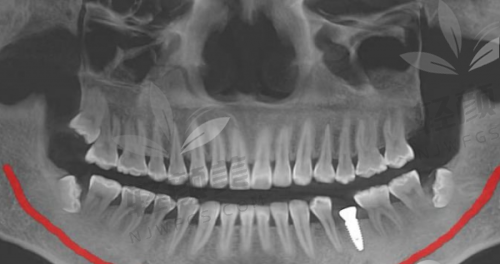

我按照预约的时间来到了重庆团圆口腔,医院的环境特别干净整洁,工作人员也都特别热情,一进门就有人引导我去挂号、填资料。见到李志锋医生后,他特别和蔼可亲,详细地询问了我的牙齿情况和病史,还耐心地听我倾诉了牙齿缺失以来的烦恼。然后他给我做了全方面的口腔检查,包括拍X光片和CT,通过这些检查,李医生精细地了解了我牙槽骨的情况。之后,他根据我的检查结果,给我制定了详细的种植牙方案。他给我推荐了以色列种植牙,说这种种植牙的材质和性能都特别好,而且价格也比较实惠,3500起就能做,性价比非常高。他还跟我解释了整个种植过程和术后的注意事项,让我心里有了底。